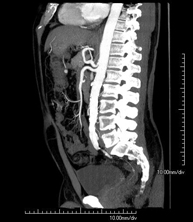

Centro Médico Teknon cuenta con un método de última generación que permite la reconstrucción tridimensional del órgano estudiado o bien la obtención del órgano en los tres planos del espacio. La Tomografía Computarizada, mediante un movimiento de rotación, envía emisiones de rayos X sucesivas a uno o varios detectores. Estos datos se integran en un sistema único que los exporta en un "volumen" de imágenes que representan la región explorada. De este modo se obtienen imágenes detalladas, con una resolución de densidad muy superior a la de la radiología convencional.

- Abdomen y pelvis- TC Abdomen Prueba diagnóstica que consiste en obtener imágenes del abdomen de alta definición anatómica (hígado, vesícula biliar, vía biliar, páncreas, bazo, estómago, intestinos, riñones, estructuras vasculares, vejiga, útero y ovarios, etc.) mediante el empleo de un equipo de TC (Tomografía Computarizada). Dichas imágenes se estudian posteriormente en una estación de trabajo que permite reconstrucciones bidimensionales en diferentes planos del espacio, y también reconstrucciones 3D (volumétricas). La mayoría de estudios requieren el empleo de contraste yodado para mejorar la definición de las imágenes. Prueba diagnóstica que consiste en obtener imágenes del abdomen de alta definición anatómica (hígado, vesícula biliar, vía biliar, páncreas, bazo, estómago, intestinos, riñones, estructuras vasculares, vejiga, útero y ovarios, etc.) mediante el empleo de un equipo de TC (Tomografía Computarizada). Dichas imágenes se estudian posteriormente en una estación de trabajo que permite reconstrucciones bidimensionales en diferentes planos del espacio, y también reconstrucciones 3D (volumétricas). La mayoría de estudios requieren el empleo de contraste yodado para mejorar la definición de las imágenes.

- TC Abdominopélvico Prueba diagnóstica que consiste en obtener imágenes bi y tridimensionales del abdomen y de la pelvis de alta definición anatómica (estructuras óseas, estructuras vasculares, hígado, páncreas, vesícula biliar, riñones, glándulas suprarrenales, bazo, intestino delgado y grueso, vejiga, útero y ovarios, próstata y vesículas seminales, uréteres, etc.) mediante el empleo de un equipo de TC (Tomografía Computarizada). La mayoría de estudios requieren el empleo de contraste yodado. Prueba diagnóstica que consiste en obtener imágenes bi y tridimensionales del abdomen y de la pelvis de alta definición anatómica (estructuras óseas, estructuras vasculares, hígado, páncreas, vesícula biliar, riñones, glándulas suprarrenales, bazo, intestino delgado y grueso, vejiga, útero y ovarios, próstata y vesículas seminales, uréteres, etc.) mediante el empleo de un equipo de TC (Tomografía Computarizada). La mayoría de estudios requieren el empleo de contraste yodado.